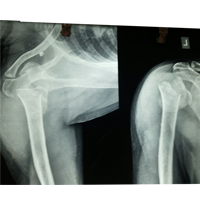

Case:2 Fracture of Neck Humerus with Fracture of Greater Tuberosity

Pre-Op AP

Pre-Op Trausaxillay